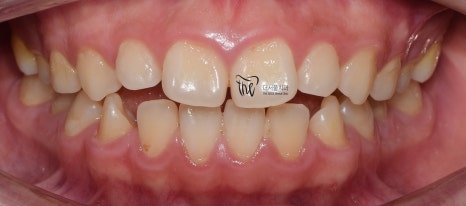

그리고, 정면 및 측면에서 본 모습으로는

살짝 개방교합(Open bite)의 형태를 보여줍니다.

그러면서, 치아들 간의 공간이 조금씩

떨어져 있는 것을 볼 수 있습니다.

마치, 치간이개와 같은 느낌을 받을 수 있으며

앞니들이 앞쪽으로 많이 뻐드러져 있는 형태를

띄고 있습니다.

이럴 경우에는, 무턱 의 증세가 더 뚜렷하게

나타날 수 밖에 없는 상황이 됩니다.